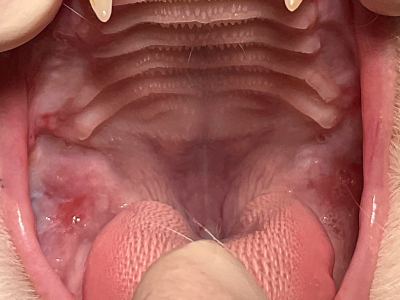

術前

のどまで真っ赤に腫れ上がっていて、これでは食事はつらいことでしょう。